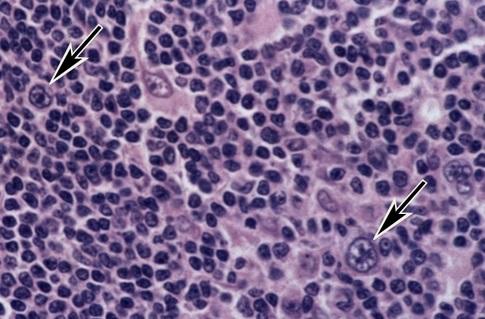

Микропрепараты: Лимфогранулематоз и Нодулярный Склероз

Раздел: Секреты мастерства